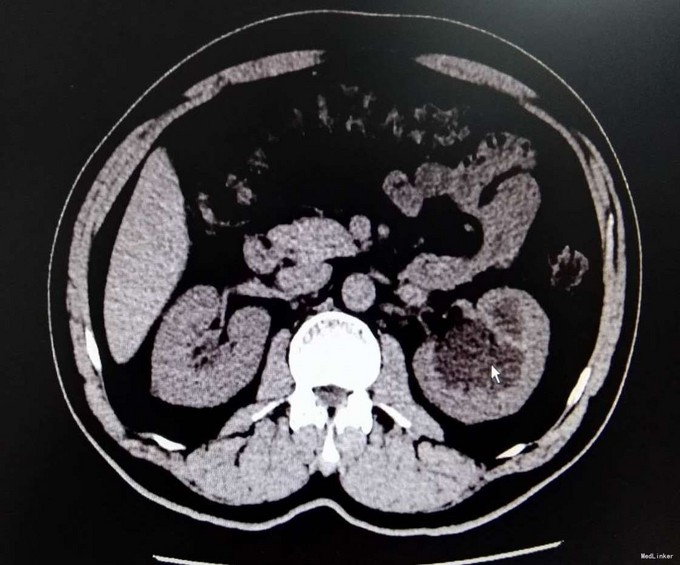

3、查体:未见明显阳性体征 4、辅助检查:外院平片:双肾多发结石;我院CTU:双肾多发结石,左侧肾盂输尿管连接处结石,并双肾积水,左肾明显,双侧肾盂、输尿管炎症。

5、诊断:肾结石(双肾多发结石) 6、治疗:入院后完善相关检查,双肾CTU:双肾多发结石,左侧肾盂输尿管连接处结石,并双肾积水,左肾明显,双侧肾盂、输尿管炎症。排除手术禁忌症后行左侧PCNL术,术后恢复良好,拔出肾造瘘管后,先出院休息,2周后返院进一步治疗